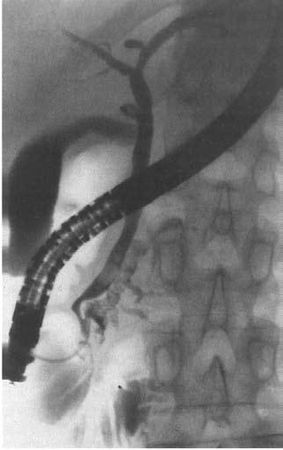

Рис. 132. Ретроградная панкреатикография при хроническом панкреатите. На снимке виден резко расширенный главный панкреатический проток

Если решено осуществить РХПГ, в фатерову ампулу через канал фиброскопа вводят специальный тефлоновый катетер с наружным диаметром 1,8 мм, а через него – водорастворимый рентгеноконтрастный препарат (верографин, урографин и др.), избегая избыточного давления, после чего делают снимок (рис. 136).

На рентгенограмме могут быть обнаружены характерные для ХП признаки: расширение главного панкреатического протока иногда в виде контрастной "цепи озер", наличие в протоке стриктур, конкрементов, а также сообщающихся с протоком полостей (псевдокист).